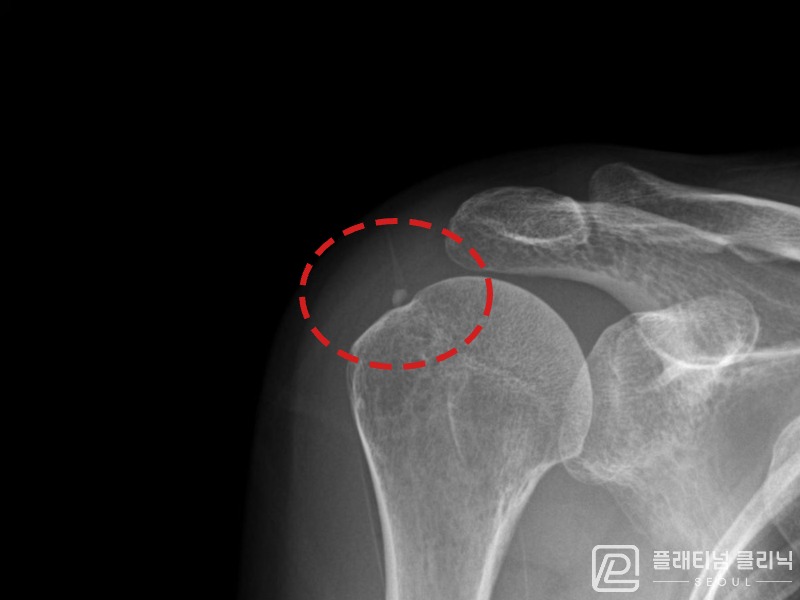

[촬영시기:21.09.02~21.10.07]

[석회분쇄흡입술] 좌측 어깨 통증으로 팔을 옆으로 올리기 어려워진 60대 남성 환자로, X-ray에서 좌측 극상근건 내 석회 침착이 확인되어 석회분쇄흡입술을 시행하였습니다.